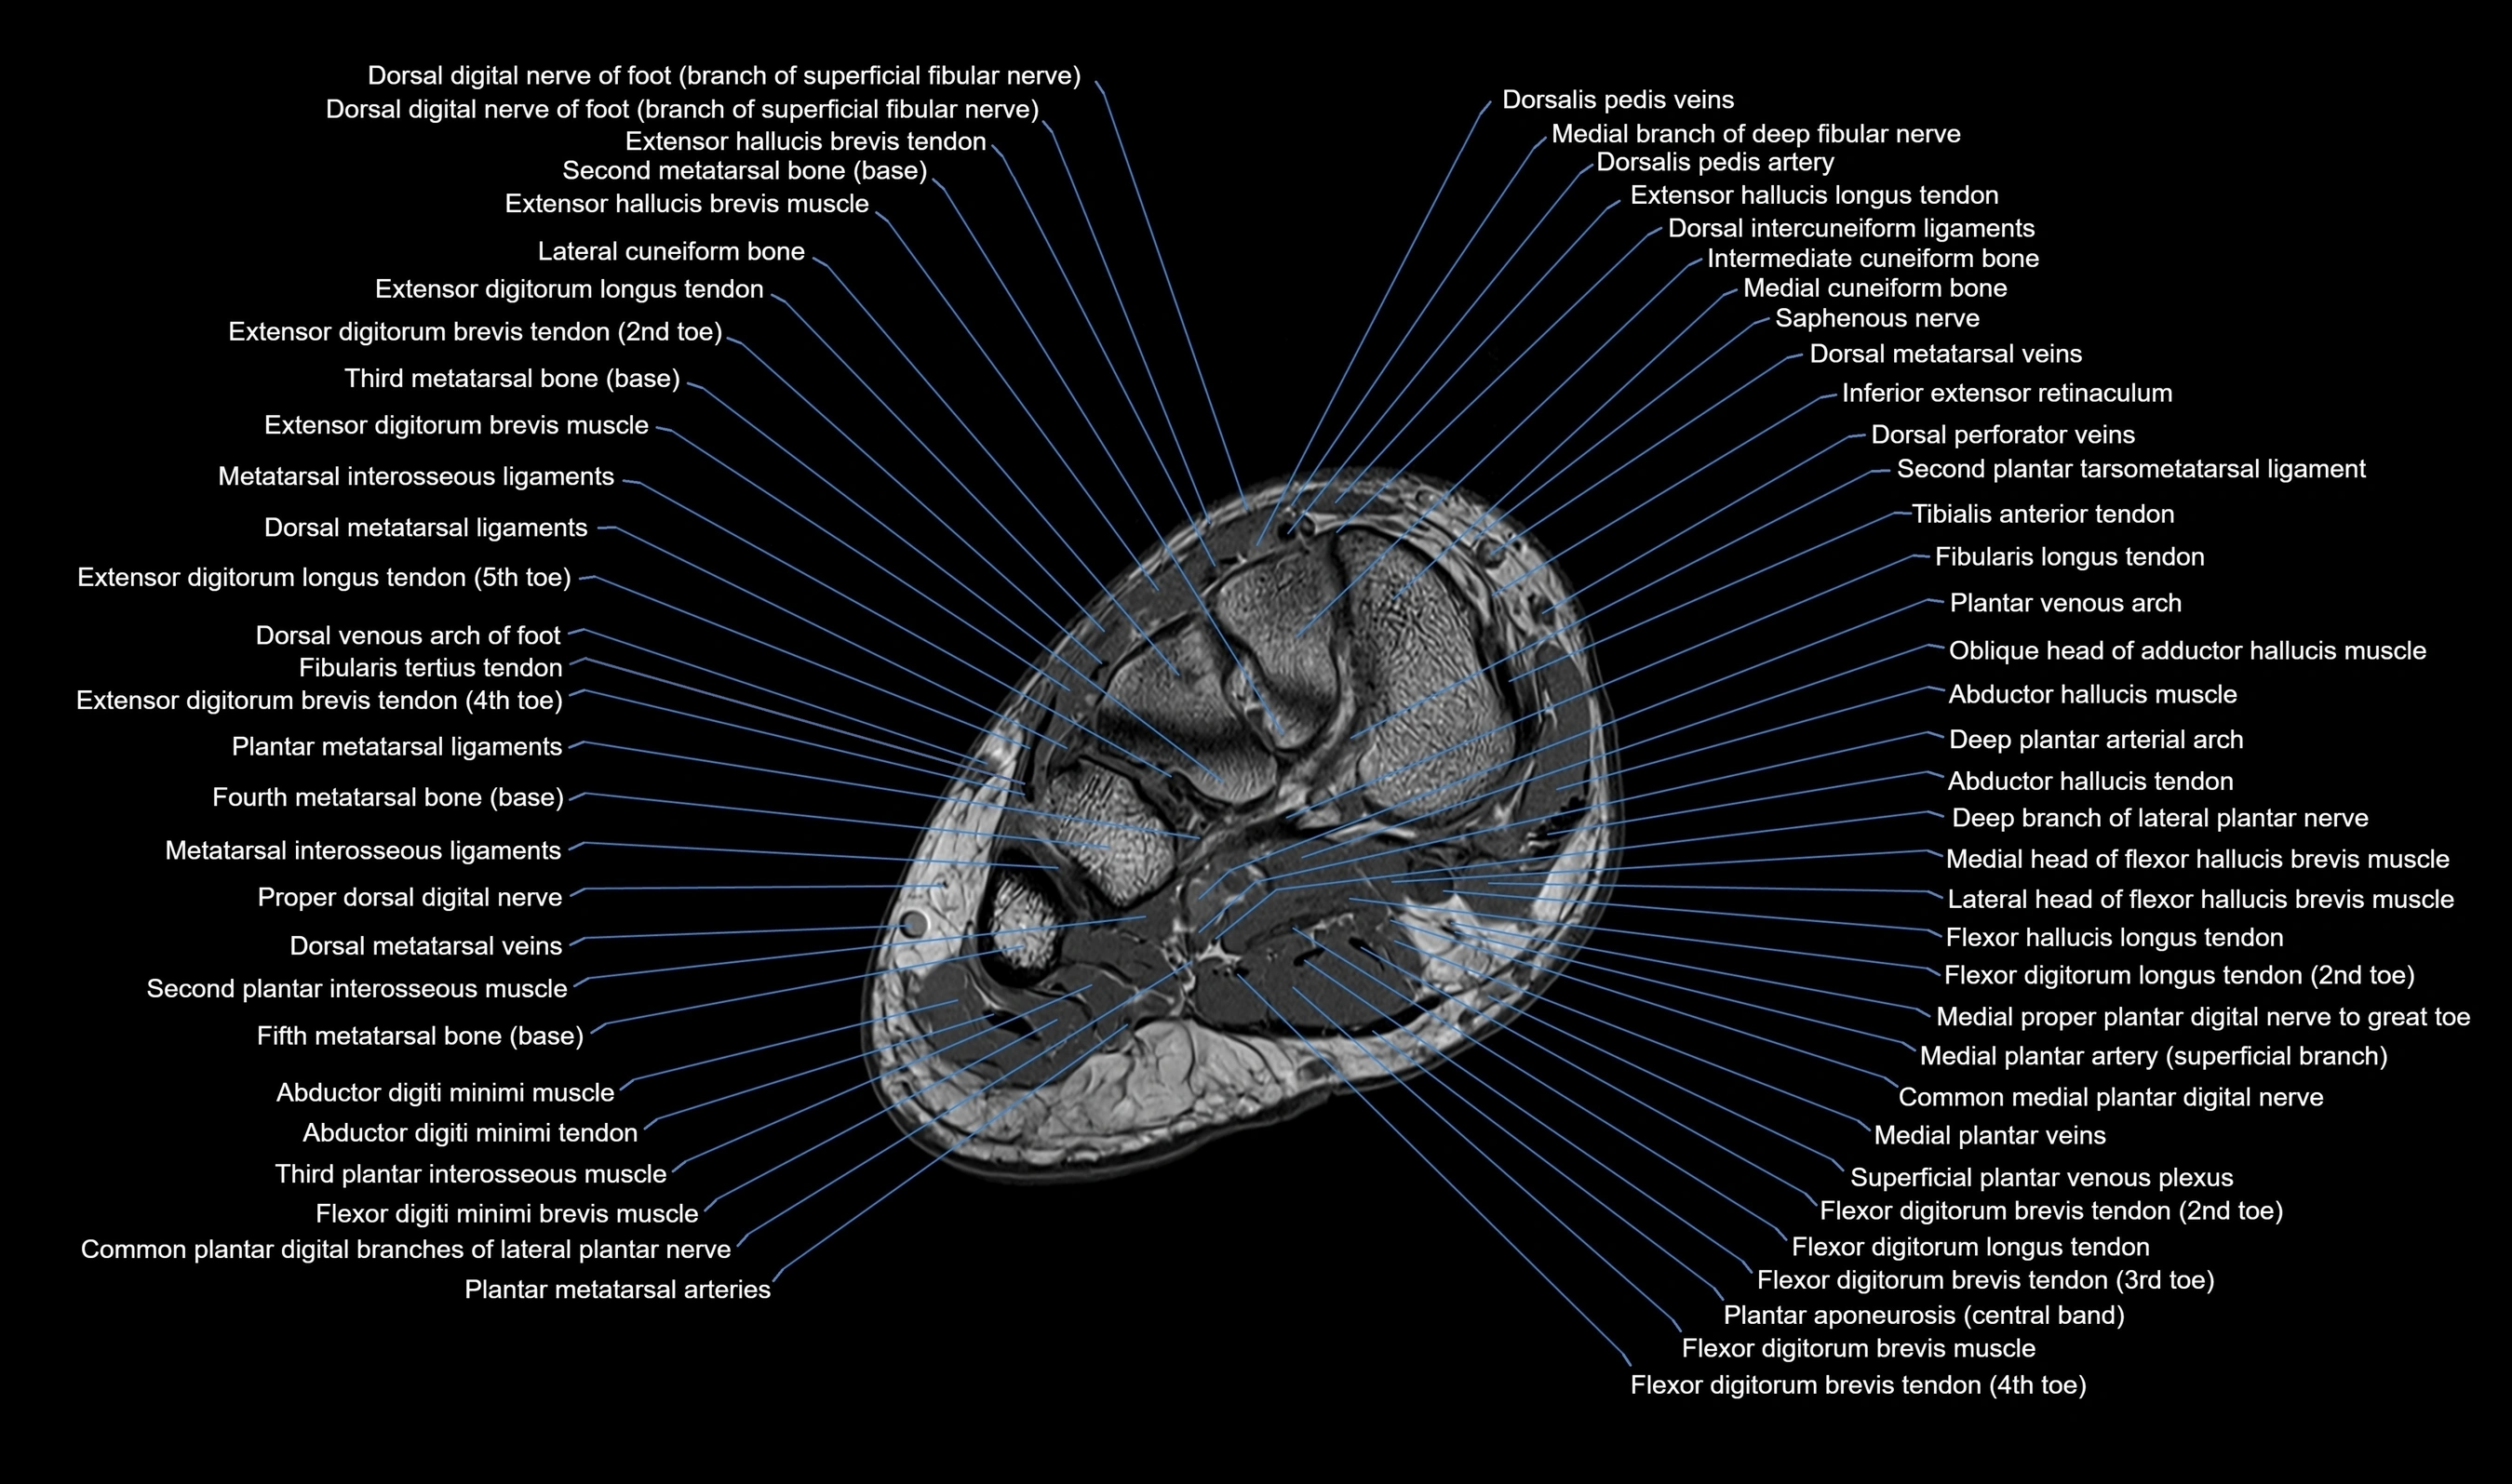

MRI image